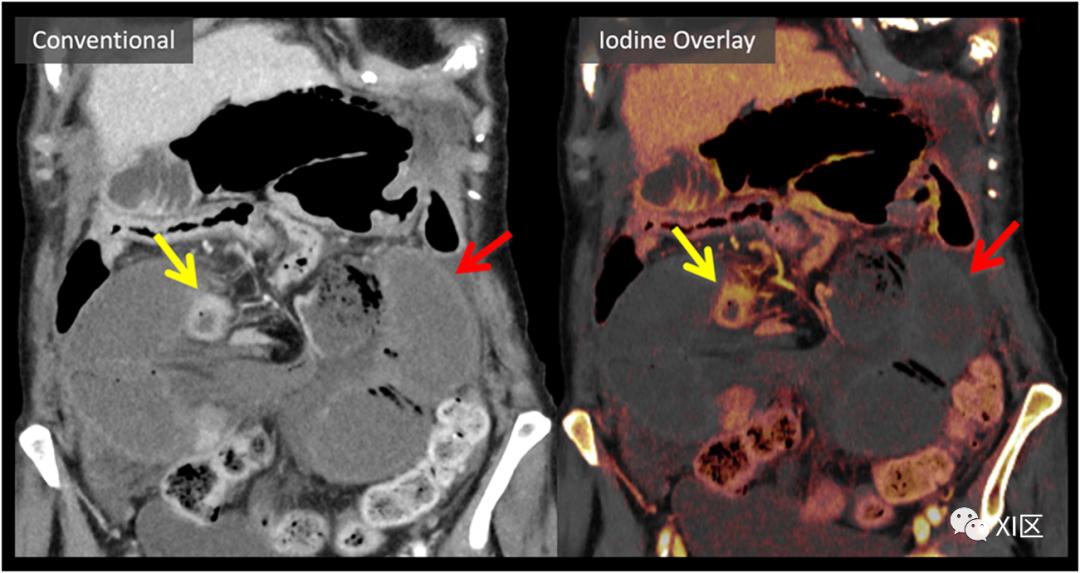

肠道状况

DECT碘后处理有助于评估肠壁强化,特别是在肠缺血或肠梗阻相关损害的情况下,有助于识别肠壁缺失或差异性强化。如图8所示,当增厚的缺血肠壁包含出血时,这可能对常规成像特别具有挑战性,而出血可能被误认为是残余肠壁增强。碘图改善了细微增强差异的显著性,可能有助于早期识别和外科优先处理有风险的肠道。

胰腺炎与胰腺坏死的鉴别诊断

传统的影像学方法难以区分水肿性胰腺实质和早期坏死。图9展示了碘图在更好地识别胰腺坏死(急性胰腺炎的一个重要预后指标)方面的应用。DECT也可能有助于评估复杂的胰腺和胰周积液,以及胰腺炎的血管并发症。